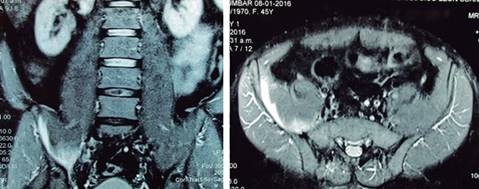

Hombre de 45 años, con padecimiento de 18 días de evolución originado en la realización de dos series de 30 movimientos (flexión de cadera con elevación bilateral de las extremidades pélvicas con extensión de rodilla en posición supina); en los 15 minutos posteriores presentó dolor intenso (10 en la EVA) en la zona lateral de la cresta iliaca derecha con irradiación al glúteo, región inguinal y fosa iliaca derecha, con imposibilidad para la flexión de la cadera y deambulación dolorosa. Efectuó reposo por tres días y analgésico; con paraclínicos normales, al no tener cambios en la sintomatología, se le solicitó una resonancia magnética de la columna lumbar, donde se detectó protrusión discal L4/L5 central y hernia discal L5/S1; se prescribió pregabalina a dosis de 75 mg para incrementarla a 150 mg a los cuatro días; con dolor de 7 en la EVA, fue canalizado a rehabilitación. A la exploración en rehabilitación, se encontró postura en bipedestación con semiflexión de cadera, ambulación con ayuda de andador, dolor intenso al intentar movilidad activa en flexión y/o rotación interna de la cadera, prueba de Thomas positiva, cuádriceps derecho con calificación 3/5. El anillo inguinal estaba normal, se ubicó zona de hiperestesia en el territorio del nervio femoral derecho en el muslo y la pierna; se realizó el diagnóstico presuncional de ruptura muscular parcial del psoas iliaco derecho. Se solicitó resonancia magnética de la pelvis (Figura 2), corroborando ruptura parcial grado III del músculo iliaco derecho, con sangre entre sus fibras. Se le manejó inicialmente con reposo, con cadera en flexión por tres días; posteriormente, extensión paulatina de la cadera a posición neutra por cinco días más, marcha con ayuda de muletas axilares con apoyo parcial; farmacológicamente, con tramadol a dosis de 10 mg cada seis a ocho horas aunado a paracetamol 500 mg. Al octavo día, se inició manejo con diatermia a la fosa iliaca derecha, ejercicios activo-asistidos de flexo-extensión de cadera por ocho días; se agregaron ejercicios en bicicleta estacionaria, electroestimulaciones y fortalecimiento del cuádriceps derecho con técnica de DAPRE (ejercicios de resistencia progresiva con incremento diario). Fue dado de alta a las seis semanas con indicaciones de no efectuar el tipo de ejercicio que desencadenó el cuadro.

Mujer de 68 años que acude a rehabilitación con dolor de un mes de evolución, localizado en región inguinal derecha, el cual inició inmediato a resbalón en tina de baño, obligando a la paciente a efectuar flexo-abducción forzada (grand écart) de ambas articulaciones coxofemorales, quedando la derecha hacia atrás y afuera; el dolor con intensidad 7/10 en EVA, con irradiación a cara anterior de tercio superior y medio de muslo ipsilateral, mejorando con analgésicos sin desaparecer y con incremento al subir o bajar escaleras. A la exploración: postura normal; marcha claudicante a expensas de miembro pélvico derecho, con semiflexión de cadera al apoyo ipsilateral; dolor a la palpación a 3 cm por debajo de espina iliaca anterosuperior derecha y a lo largo del tercio externo del ligamento inguinal ipsilateral, incrementándose con estiramiento pasivo del cuádriceps ipsilateral; arcos de movimiento de cadera completos, excepto la rotación interna de cadera derecha dolorosa, resto de arcos de movilidad en miembros pélvicos completos, el examen clínico muscular mostró: psoas iliaco derecho en 4/5, cuádriceps derecho 3/5 por dolor en cara anterior de muslo y región inguinal ipsilateral, resto de músculos de miembros pélvicos con calificación 5/5; reflejos osteotendinosos, sensibilidad y llenado capilar normales. Con el diagnóstico presuncional de lesión del recto femoral del cuádriceps derecho se solicita placa simple AP de pelvis y resonancia magnética de pelvis (Figura 3) encontrando: en placa simple datos compatibles con lesión del rodete glenoideo en su porción anteroexterna y coxartrosis ipsilateral; en la resonancia magnética se observa líquido (sangre) rodeando al músculo rector femoral disecándolo. Se le prescribe reposo relativo, uso de bastón a mano contralateral, paracetamol 500 mg/TID, además de tramadol solución, 10 mg como dosis de rescate en caso de dolor intenso, se aplicaron sesiones de ultrasonido cada tercer día (en número de 15), con ejercicios de estiramiento paulatino de cuádriceps, se dio de alta asintomática.

Figura 3: Imagen de resonancia magnética de pelvis en cortes axiales, ponderadas en T2, mostrando en (A) presencia de líquido (sangre) que diseca al músculo recto femoral del cuádriceps a nivel de articulación coxofemoral (flecha); en (B) a nivel del trocánter mayor el líquido rodea completamente al rector femoral disecándolo (flecha).

En relación a la lesión del músculo psoas iliaco, en la mayoría de los gimnasios aún se efectúan rutinas de ejercicios con poca o inadecuada supervisión; un ejemplo es la elevación de ambas extremidades inferiores con rodillas en extensión en posición supina,6 con la suposición de que dicho movimiento es útil para fortalecer los músculos abdominales. Desde el punto de vista biomecánico, este movimiento es efectuado por el complejo muscular psoas iliaco, que por su inserción proximal, durante su acción ocasiona hiperlordosis lumbar, lo que hace vulnerable al psoas iliaco; si a eso agregamos que durante el descenso de las extremidades inferiores, la contracción es de tipo excéntrico, actuando sobre un largo brazo de palanca, se incrementa el riesgo de desgarro muscular. La lesión en su inserción distal es más frecuente, pero puede observarse también en sus inserciones proximales (como en el caso presentado); el nervio crural puede afectarse por sus relaciones anatómicas en 37 a 57% de los casos, produciendo su parálisis por compresión o irritación. En relación con la prevalencia, las lesiones se presentan habitualmente en personas jóvenes durante la práctica deportiva. Las manifestaciones más frecuentes son: dolor inguinal y/o dolor lumbar o en el flanco ipsilateral, que se incrementa con la flexión activa de cadera. A la exploración se encuentra imposibilidad para flexionar la cadera ipsilateral a la lesión; existe dificultad para la marcha y paresia del cuádriceps, el intento de extender pasivamente la cadera agrava el dolor (signo invertido del psoas).7 Se pueden presentar parestesias y alteración de la sensibilidad cutánea en el territorio del nervio femoral. Los pacientes con grandes hematomas del psoas iliaco pueden presentar signos de hipovolemia, ya que el músculo puede contener un gran volumen sanguíneo. Al diagnóstico se llega por un interrogatorio adecuado y exploración física completa, corroborándose con apoyo de imagen. En todos los individuos es indispensable comprobar su estado de coagulación. La ecografía abdominal puede aportar mucha información para detectar estas lesiones; no obstante, la tomografía, la angiotomografía y la resonancia magnética tienen mayor sensibilidad y especificidad. La tomografía es útil para diferenciar los hematomas de otras lesiones retroperitoneales como abscesos y tumores; la angiografía puede actuar de manera diagnóstica y terapéutica al ser posible la embolización del vaso sangrante. Entre los diagnósticos diferenciales8 de este cuadro se encuentran apendicitis aguda, abscesos musculares, tumores retroperitoneales, cólico nefrítico, coxartrosis o hemartrosis de cadera, fracturas de las espinas iliacas posterosuperior y anterosuperior, así como hernias discales. Cuando no existe antecedente traumático, es indispensable realizar pruebas de coagulación y descartar discrasia sanguínea o el uso de anticoagulantes. La cirugía estaría indicada si hay progresión del sangrado, parálisis completa sin signos de recuperación en lo inmediato o ambos. La neuropatía femoral es habitualmente reversible; el tiempo para la recuperación es variable y a veces prolongado. Los pacientes hemofílicos se tratan con reposición de factor VIII o IX hasta que cesa el sangrado y en ellos está contraindicada la cirugía. El tratamiento de los hematomas del psoas iliaco es controvertido; en hematomas de pequeño o moderado tamaño sin repercusión hemodinámica, el manejo es conservador, con reposo absoluto y analgesia adecuada; puede llegar a requerirse la aplicación de tracción del miembro ipsilateral para rectificar la contractura refleja de la cadera, alinear la articulación y disminuir el dolor, así como un programa de rehabilitación. El manejo de la hemostasia resulta en extremo importante. En el caso de grandes hematomas que causen compresión importante con alteración funcional de las estructuras adyacentes existe indicación quirúrgica9 excepto en pacientes hemofílicos, en donde está contraindicada la cirugía.

El músculo rector femoral (RF) es el único músculo biarticular del cuádriceps, es el músculo más frecuentemente lesionado en el muslo anterior, especialmente en atletas, las lesiones en su inserción proximal son menos frecuentes, pudiendo originarse en tres puntos distintos: a) en la entesis (inserción en la espina iliaca anteroinferior), b) en el tendón y, c) en la unión músculo-tendinosa. En niños se presenta como avulsión de la espina iliaca anteroinferior;10 las rupturas traumáticas (como en este caso) y la tendinitis calcificada se observan en adultos; la lesión traumática puede ser subdiagnosticada, principalmente en el adulto mayor confundiéndose con coxartrosis u otras causas de dolor inguinal. La lesión traumática del rector femoral se presenta durante la hiperextensión de cadera con rodilla en flexión (como en el caso presentado) o como resultado de una contracción excéntrica del cuádriceps. El ultrasonido apoya el diagnóstico; sin embargo, el estudio de elección es la resonancia magnética.11 El tratamiento habitualmente es conservador, requiriéndose cirugía en casos seleccionados en atletas.4